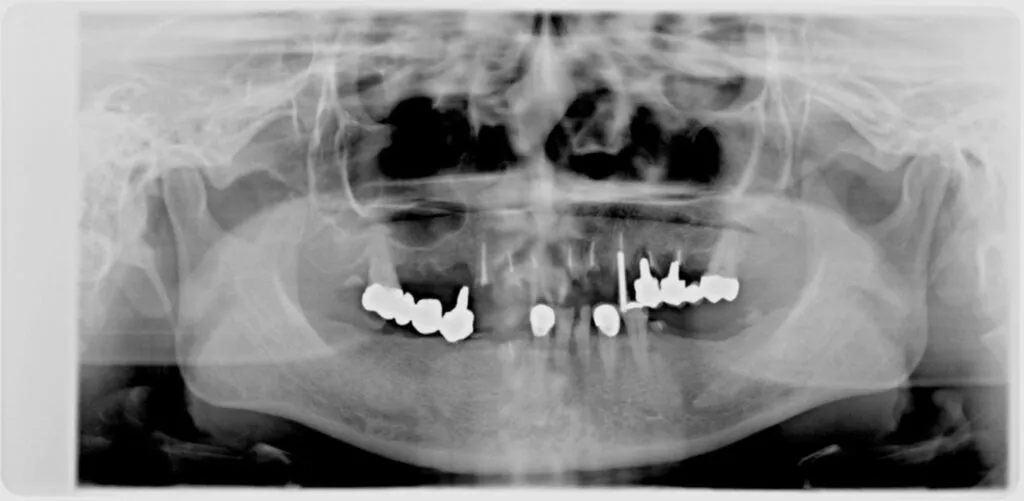

症例

患者様のお悩み | 食事ができない |

|---|---|

治療法・使用素材 | インプラントを用いた全顎的咬合治療 |

患者様の年代 | 40代 |

治療開始年齢 | 49歳 |

治療にかかった期間 | 2年 |

性別 | 女性 |

この治療のリスクについて | |

治療にかかった費用 | 600万 |

治療前